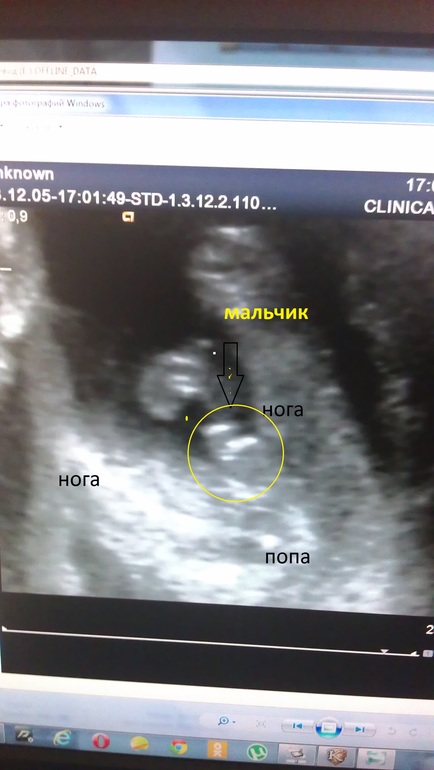

Я чувствую всеми фибрами души, что будет мальчулька и жду его собственно. И на фото узи я чётко вижу яйки))) врач ржёт, говорит, к окулисту направлю, если не отстанешь. Вот фото первое, вид со стороны попки, слева ножка, справа согнутая ножка, ребёнок на спине чуть завалившись на бок, между ножек ведь есть округлость указанная стрелкой!

Второе фото это срез поперёк и стрелка указывает на конкретные яички и писюлю!!!! А она пишет девочка.

а вот дочка на сроке 21 неделя. Вид со стороны попки, одна ножка согнута